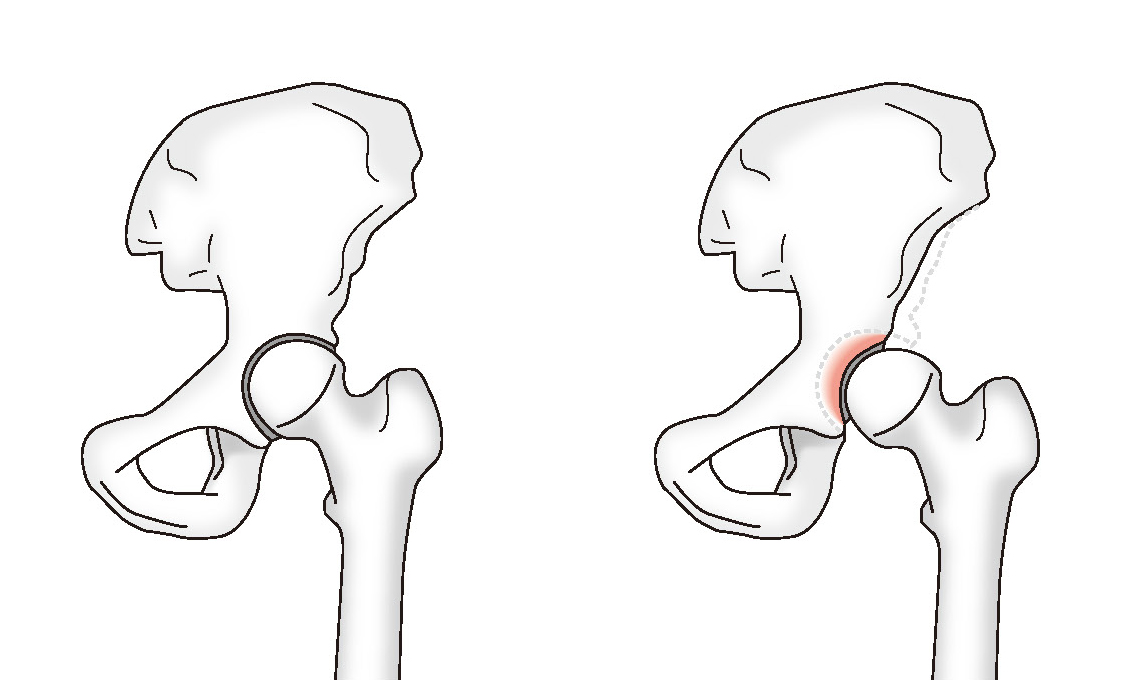

正常な股関節 臼蓋形成不全

変形性股関節症は股関節の痛みの中で最も多く、軟骨のすり減りから始まって骨の変形へと進行する病気です。股関節では、大腿骨の先端にある球状の骨頭が、骨盤側にある臼蓋という受け皿に収まり、骨頭が滑らかに擦れ合って動く「球運動」をしています。ただこの臼蓋は、生まれつきかぶりが浅いなど不完全な形の方がいて、これが臼蓋形成不全と呼ばれる変形性股関節症の主な原因のひとつです。臼蓋形成不全は女性に多く、遺伝的要素も関係するといわれています。

臼蓋のかぶりが浅いと、狭い面積で骨頭から伝わる体重を受け止めることになり、骨頭と臼蓋の間にある軟骨がダメージを受けます。また、股関節の安定性が得られず、球運動が不規則になることで軟骨のすり減りが進みます。